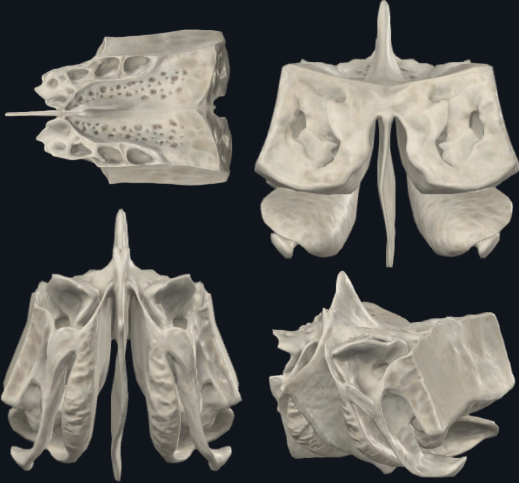

Hueso Etmoides

Cuboideo

Muy ligero debido a las cavidades neumáticas que lo conforman (celdillas etmoidales)

Celdillas etmoidales

Cavidades neumáticas. Dan volúmen con poca masa al cráneo.

Laberintos Etmoidales

Forma cuboidea

Contiene los cornetes superiores y medios

Contiene muchas cavidades neumáticas

Celdillas etmoidales, se dividen en anteriores y posteriores